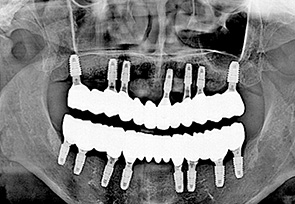

before

after